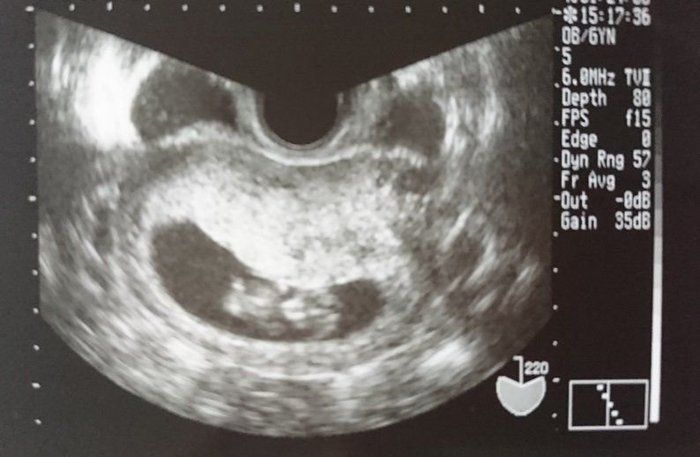

チャーミー小結さんの妊娠9週目のエコー写真

何となく頭と胴体の区別が出始め、胎芽から胎児とよばれるようになりました。スリムな人だとまだおなかの膨らみが分からない頃ですが、嬉しくてウエストノーマークのマタニティ服を着て過ごしていました。